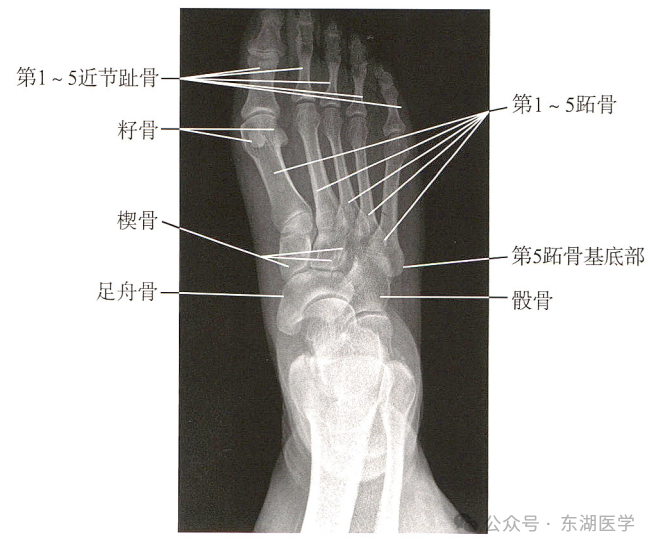

足以骨骼为支架,包括7块跗骨、5块跖骨、14块趾骨,彼此间借关节和韧带相连接。

成人足正、斜位X线解剖

1. 甲粗隆;2.踇趾远节趾骨;3. 趾间关节;4.踇趾近节趾骨;5. 第1跖骨头;6. 籽骨;7. 第1跖骨干; 8. 第1跖骨基底部;9. 内侧楔骨;10. 中间楔骨;11. 外侧楔骨;12.足舟骨;13. 距骨;14.远节趾骨;15.中间趾骨;16. 近节趾骨;17. 跖趾关节;18.第2跖骨基底部;19.第3跖骨基底部;20.第4跖骨基底部;21.第5跖骨基底部;22.骰骨;23. 跟骨